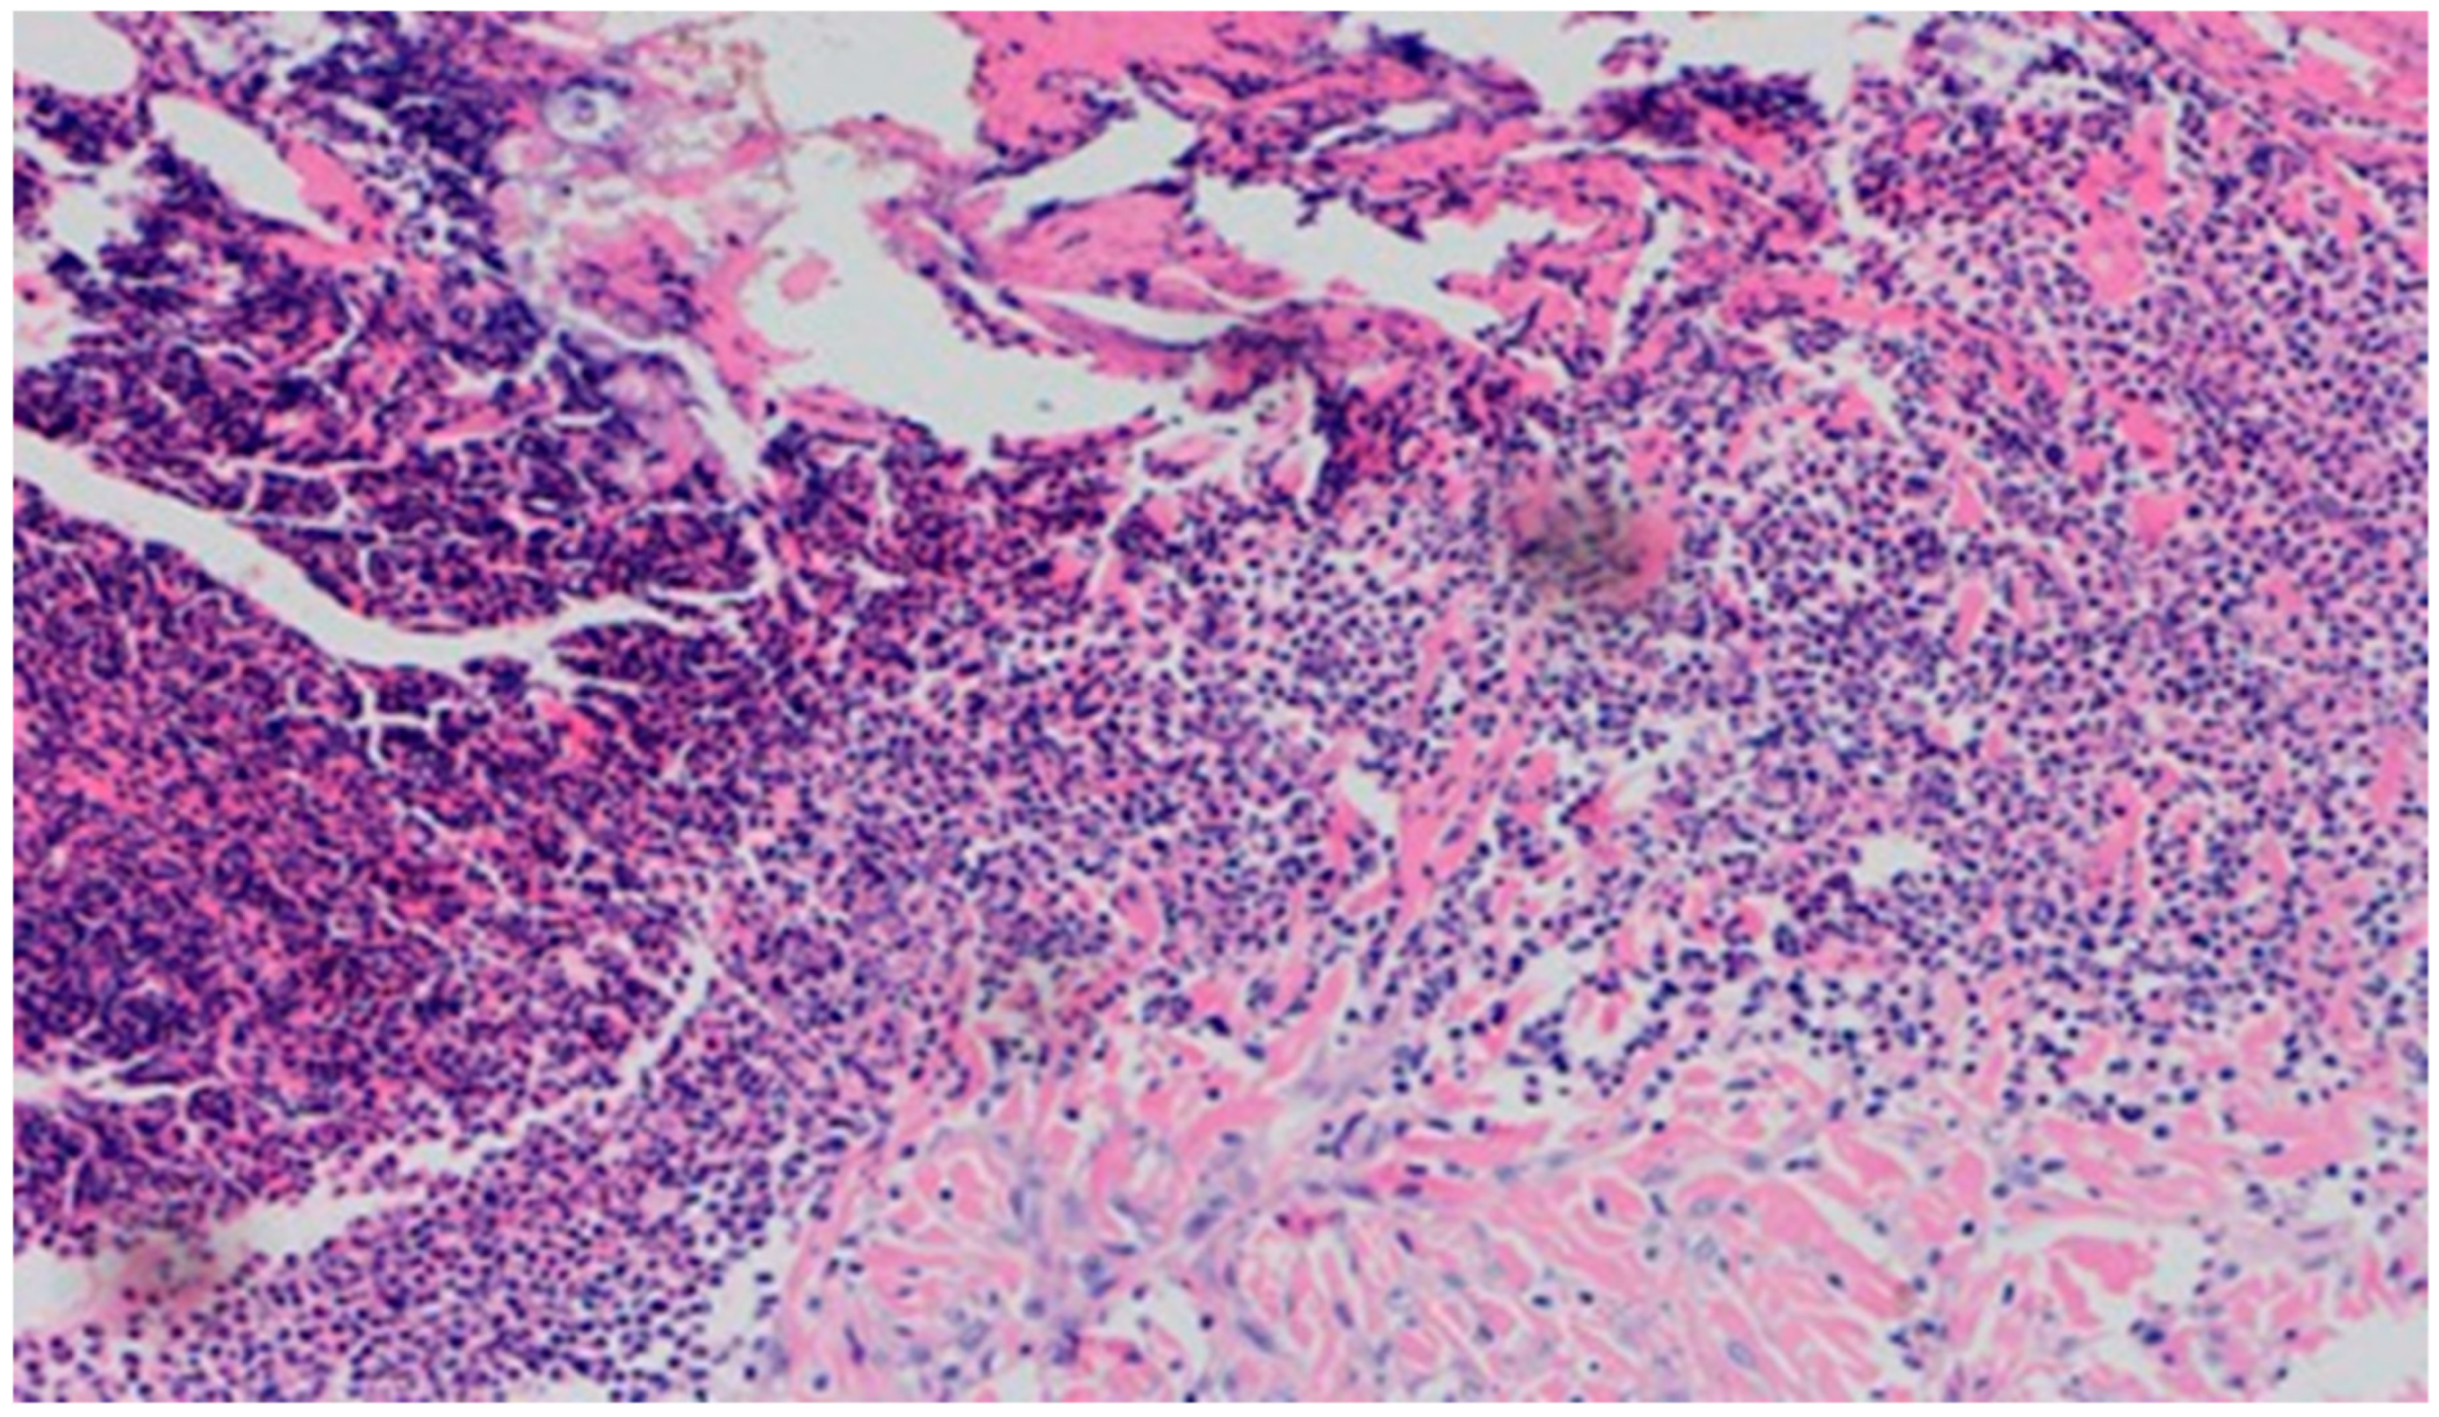

On day 10, all wounds in the control and experimental groups were characterized by a moderate inflammatory infiltration, with a predominance of granulocytes, reaching the dermis. In the experimental group D1, inflammation was at the same level as on the 5th control day. The experimental group D2 and the control group K, treated successively with the 1% nanosilver ointment and sulfathiazole, showed a greater intensity of inflammation in relation to the 5th control day. In group D3, treated with a mixture of 1% propolis and 1% nanosilver, a regression of the inflammatory infiltration, from large to medium, and depth, from adipose tissue to the dermis, was observed. In the experimental group D1, treated with the 1% propolis ointment and control K, treated with sulfathiazole, on day 10, a slight epidermization appeared. On day 10, additionally, all the wounds from the experimental and control groups showed slight superficial necrosis and were characterized by a moderate neovascularization. The histopathological findings from day 10 are presented in Table 9 and Figure 15, Figure 16 and Figure 17.

On day 15, the wound samples examined differed significantly, depending on the therapeutic agent used. The wound treated with the 1% propolis ointment was characterized by a consistently slight epidermization and moderate neovascularization, as was on day 10; however, the wound showed no foci of superficial necrosis. Additionally, the type of inflammatory infiltration changed into a lymphocytic-granulocytic one. The wound in the experimental group D2, treated with the 1% nanosilver ointment, and the wound in control group K, treated with sulfathiazole, continuously showed the progression of inflammation, from moderate to severe. On day 15, the wounds from the experimental group D2 and control group K were covered with large superficial necrosis.

The wound treated with the 1% nanosilver ointment showed high neovascularization, with no epidermization at the same time. The wound from group D3, treated with a mixture of 1% propolis and 1% nanosilver, showed a constant moderate inflammatory infiltration, however, with a change of type on day 15 to lymphocytic-granulocytic. Additionally, on day 15, the wound in the D3 experimental group was covered with a slight superficial necrosis with moderate neovascularization. The wound showed no signs of epidermization. The histopathological findings from day 15 are presented in Table 10 and Figure 18 and Figure 19.

Figure 15. Granulocytic inflammatory infiltration, medium density.

Figure 16. Slight superficial necrosis. Moderately intense granulocytic inflammatory infiltration in the dermis (40×, H-E), in the wound treated with the 1% nanosilver ointment, on day 10.

Figure 17. Focal epidermization under superficial necrosis (100×, H-E) in the wound treated with the 1% propolis ointment on day 10.